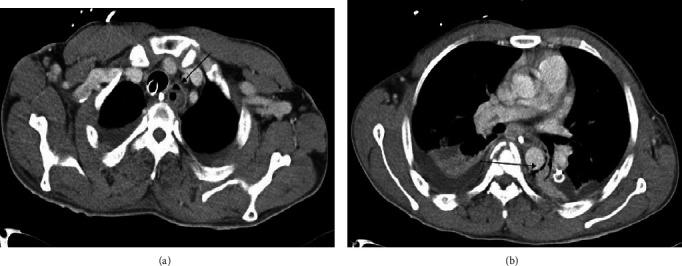

在重症监护患者中,经口或经鼻途径进行肠内喂养是一种普遍的标准做法,总体安全性良好。然而,与鼻胃管(NGT)或口胃管(OGT)插入相关的并发症在医学文献中比拔除此类导管更为常见。我们报告了一名38岁男性,他遭遇机动车碰撞,在车外被发现格拉斯哥昏迷量表评分较低。他有多发性创伤,经口气管插管并通过OGT开始肠内喂养。在喂养管周围几天内形成了食管粪石,导致拔除时需要很大力气,结果并发食管穿孔。食管损伤经保守治疗后顺利康复。虽然文献中确实存在关于食管肠内喂养粪石形成的有限病例报告,但我们认为这是首例因食管粪石形成导致OGT嵌顿后强行拔除而引起食管穿孔的病例报告。与OGT/NGT相关的发病率并不常见,可能需要高度怀疑才能识别。在拔除NGT/OGT时如果感觉到阻力,情况尤其如此。建议尽早进行胃肠病学咨询以检测和处理任何并发症,但在这种稳定的病例中其作用非常有限。此外,可以考虑早期计算机断层扫描(CT)以便及时识别食管穿孔。对于稳定的患者可以考虑非手术治疗,特别是如果漏口在食管颈部。最后,预防胜于治疗,所以通过影像学检查并测量鼻孔/口腔处的导管长度来确认NGT/OGT位置,是避免误置和并发症的关键。该病例提高了医生对这种可预防医源性事件的认识。